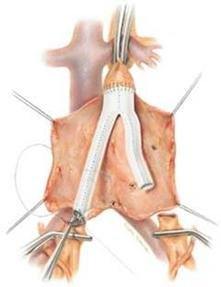

Anevrizmanın klasik cerrahi tedavisi ameliyat ile genişlemiş damar bölümünün suni bir damar ile değiştirilmesidir. Bu yöntem yaklaşık 50 yıldır kullanılmakta olup, güvenilir ve kalıcı sonuçlar sağlamaktadır. Ameliyat genel anestezi altında karından büyük bir kesi yapılarak gerçekleştirilir ve bir sorun olmadığı takdirde hastalar ameliyat sonrası 7-10 gün içinde taburcu edilirler. Hastaların normal yaşamlarına dönmeleri 1-2 ay sürebilir. Bu yöntem anevrizmayı tamamen tedavi edebilen bir yöntemdir. Ancak büyük bir ameliyat olmasından dolayı ameliyata bağlı ölüm riski ortalama %5 dir.

Bentall prosedürü ile asendan aort anevrizması tamiri (yapay aort kapağı ve yapay damar kullanılarak)

Cabrol prosedürü ile asendan aort anevrizması tamiri (yapay aort kapağı ve yapay damar kullanılarak)